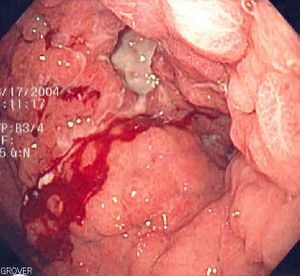

النَّزْف الوعائي Bleeding رشْحُ الدم من الأوعية الدموية. ويحدث عندما يكون هناك جرح في الشرايين أو الأوردة أو الشّعيرات. تحدث الجروح بسبب الإصابة أو التآكل أو البلى الناتج عن شذوذات مثل القرحة أو الالتهاب أو السرطان.

أنواع النزف الوعائي. يكون الدم في الشريان أحمر صافيًا، ويخرج متدفقًا تحت ضغط كبير. ويكون النزف من الوريد معتدلاً حيث الضغط خفيف، ويكون لون الدم أحمر مزرقًا. ويرشح الدم من الشعيرات.

وقد يكون النزف خارجيًا (إلى خارج الجسم)، أو داخليًا (إلى داخل الجسم). وعندما يكون النزف في الجلد، تحدث للدم عدة تغييرات في اللون من الأزرق إلى البني. وتسمى بقع الدم الكبيرة في الجسم الكدمات بينما تسمى بقعة النزف التي في حجم رأس الدبوس الحَبَر.

- Upper gastrointestinal bleed